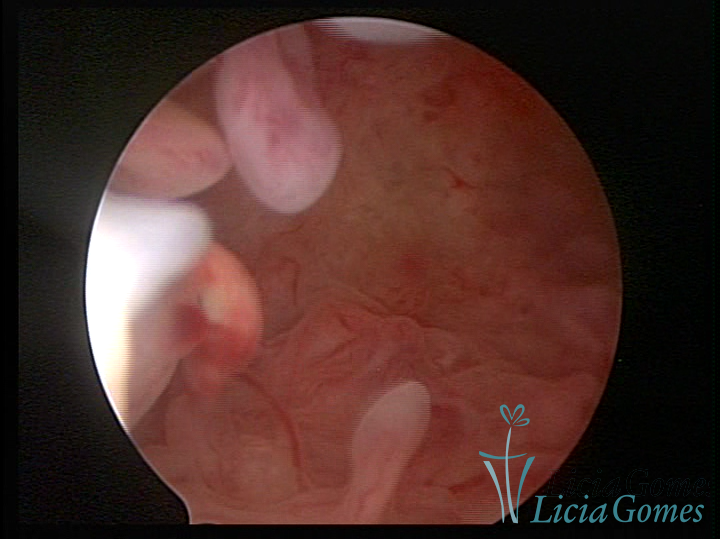

A histeroscopia permite analisar as características da superfície endometrial, não podendo avaliar a profundidade ou o grau de invasão miometrial.

Mas poderá verificar se as lesões são do tipo: focal; regional ou difusa

Este pode apresentar uma gama variável de aspectos macroscópicos, com aspecto pseudopolipoide; lembrando tecido cerebroide ou com reação deciduoide;a vascularização superficial é mais evidente e com vasos em formatos de saca-rolha ou espirais visualizando também a vascularização com atípias, com aumento do calibre dos vasos superficiais, pode ser encontrado também tecido em necrose, poderá haver um pequenos dendritos (papilomatoso).